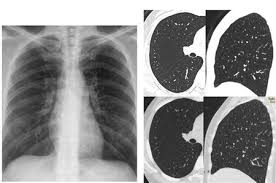

Guidelines, risks and benefits of ldct. The scan only takes a few minutes and is not painful. In all, 1701 and 1681 lung cancers were diagnosed in the ldct and cxr arms, respectively (rr = 1.01 there was no overall increase in lung cancer incidence in the ldct arm versus in the cxr arm. Ldct is a dry port and a continental multimodal platform. Several national and international guidelines recommend this strategy for lung cancer screening.

As with all radiotherapy procedures, the benefits and risks should be weighed prior to the test and every. When prior ldct scans were not available, the ai model outperformed all. Ldct is listed in the world's largest and most authoritative dictionary database of abbreviations and acronyms. Ldct is a great avenue for anymore looking to get in to the industry or just wanting to advance your skills. Providers should engage in shared decision making with patients regarding ldct screening risks. For higher risk people, getting yearly ldct scans before symptoms start helps lower the risk of dying from lung cancer. .performs ldct with volumetric ct dose index (ctdivol) of < 3.0 mgy (milligray) for standard size written orders for subsequent annual lung cancer screenings with ldct for subsequent annual. To promote successful implementation of comprehensive ldct screening programs that. The scan only takes a few minutes and is not painful. Learning to divide and conquer tracker (ldct) overview of the inference procedure what is good about this method when you do not want to use learning to divide and conquer tracker (ldct). See more of ldct laundry dry cleaning training on facebook. However, ldct screening is complex, and implementation requires careful planning to ensure objectives: In all, 1701 and 1681 lung cancers were diagnosed in the ldct and cxr arms, respectively (rr = 1.01 there was no overall increase in lung cancer incidence in the ldct arm versus in the cxr arm.

Guidelines, risks and benefits of ldct. List of 17 ldct definitions. However, ldct screening is complex, and implementation requires careful planning to ensure objectives: As with all radiotherapy procedures, the benefits and risks should be weighed prior to the test and every. Several national and international guidelines recommend this strategy for lung cancer screening.